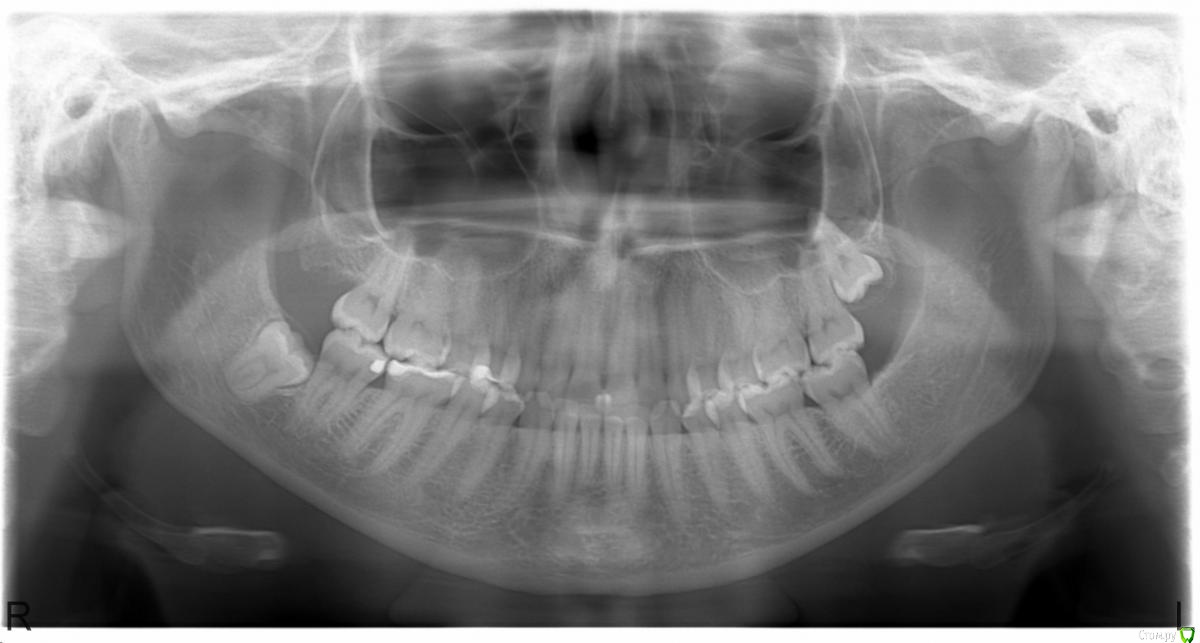

Здравствуйте! Год назад у меня откололся кусок пломбы от 6-ого зуба справа внизу. Стала забиваться пища, появились болевые ощущения. Пломбу мне поменяли, но боль не прошла. В течение двух недель сохранялся постоянный дискомфорт, спустя это время остались боль при накусывании и реакция на холодное/горячее. Кушала долгое время только на левой стороне. Плюс периодическая ноющая боль наверху над этим зубом, в каком конкретном зубе болит определить не могу - боль по всей стороне.

Полгода назад был пролечен кариес на соседнем зубе, седьмом. Стоит небольшая пломба.

Я была у многих врачей за это время. Мнения врачей очень сильно расходятся. Предлагали препарировать 6-ой, 7-ой и 4-ый зуб (единственный запломбированный наверху на той стороне, где дискомфорт).

Предполагаю, что пломба изначально откололась из-за фисташки. Возможно, при этом так же верхние зубы повредились. Но врачи сходятся в одном - проблем наверху они не видят.

Прикрепляю общий снимок и прицельный снимок шестерки. Есть КТ этой стороны, если нужно.

Я думаю, проблема у вас все-таки в 6-ом зубе. Скорее всего в нем имеется хроническое воспаление пульпы. Процесс вялотекущий, поэтому сильных болей вы не испытываете. Для подтверждения диагноза нужно сделать ЭОД. На втором месте по вероятности стоит нарушение герметичности либо микроотрыв пломбы. Решается заменой реставрации. Наличие длительной ноющей боли вверху без четкой локализации является скорее всего иррадиацией от нижнего зуба. Это тоже говорит о том, что скорее всего в 6-ом зубе пульпит.